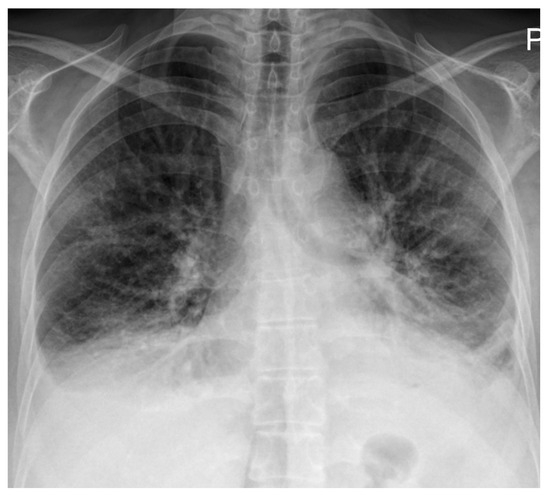

Electrocardiography demonstrated right atrial enlargement and right ventricular strain. Chest radiography (Figure 1) revealed cardiomegaly, pulmonary congestion with enlarged central pulmonary arteries, bilateral pleural effusions, and elevation of both hemidiaphragms.

Figure 1.

Chest radiography on admission demonstrating cardiomegaly with dilation of the central pulmonary arteries, increased interstitial markings with a perihilar “bat-wing” pattern, and bilateral pleural effusions, all indicative of pulmonary congestion. Bilateral elevation of the hemidiaphragms is also noted, possibly related to underlying myopathy.